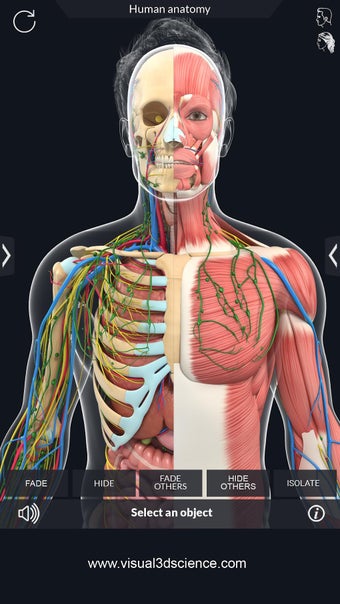

La anatomía humana es una aplicación educativa médica que te permite explorar el cuerpo humano desde todos los ángulos. Ofrece una mirada detallada a la anatomía de los diferentes sistemas, así como a los órganos y sus funciones. Es una referencia perfecta para estudiantes y profesores de medicina.

Puedes seleccionar cada parte del cuerpo por separado para ver su nombre o leer información relacionada. Puedes ocultar y mostrar cada parte del cuerpo, así como rotar 360° alrededor de un modelo 3D altamente realista. Puedes dibujar en la pantalla o compartir capturas de pantalla con tus amigos. Puedes encontrar la definición de cada parte del cuerpo y su anatomía.